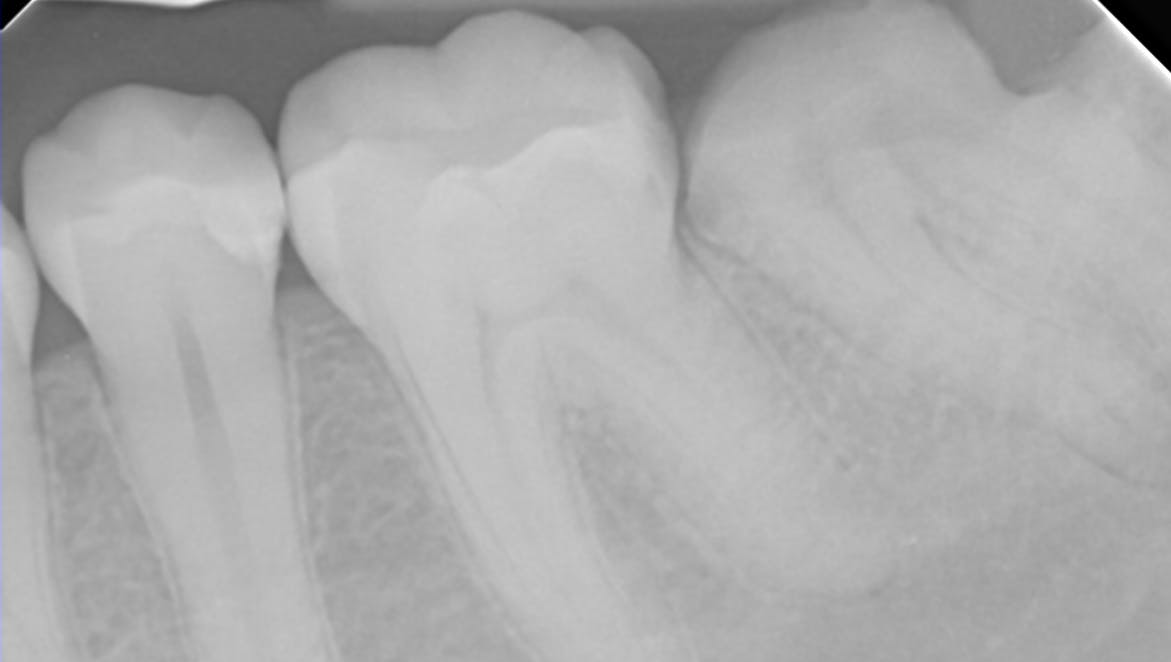

x-ray of a dental implant

This article reviews the top five drug classes beyond bisphosphonates that have demonstrated a clinically significant association with MRONJ, summarizing mechanisms, pharmacologic...